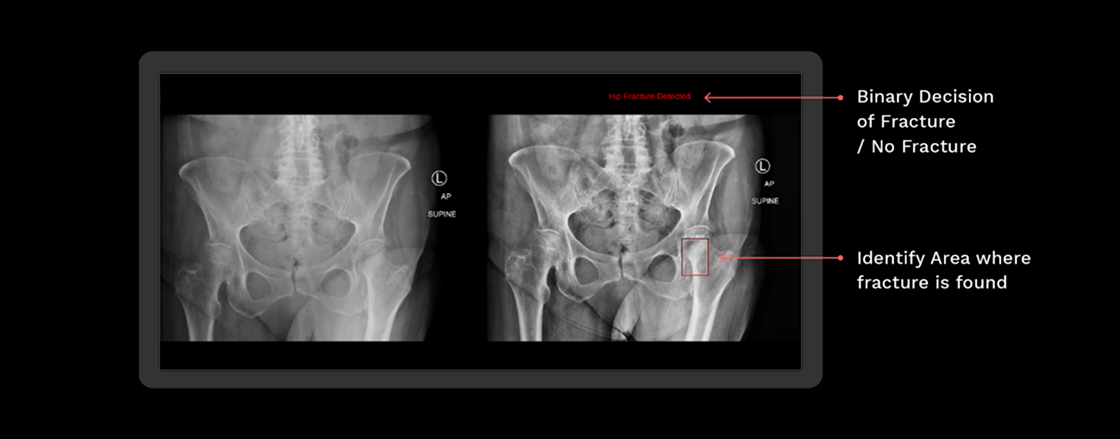

Rbfracture™

AI-powered, automatic detection of trauma-related findings

Clinical Trial

Trial showing improved diagnostic accuracy for Emergency Care residents when

reviewing hip fracture X-rays

Above shows the change using RBfracture™ has had on reviewing hip fracture images by reader group